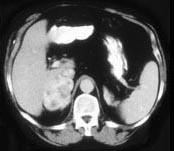

问题 女,32岁,阵发性高血压2年余,请结合所提供图像,作出诊断 ( )

选项 A、左肾上腺嗜铬细胞瘤 B、左肾上腺淋巴瘤 C、左肾上腺腺癌 D、左肾上腺转移瘤 E、左肾上腺腺瘤

答案 A